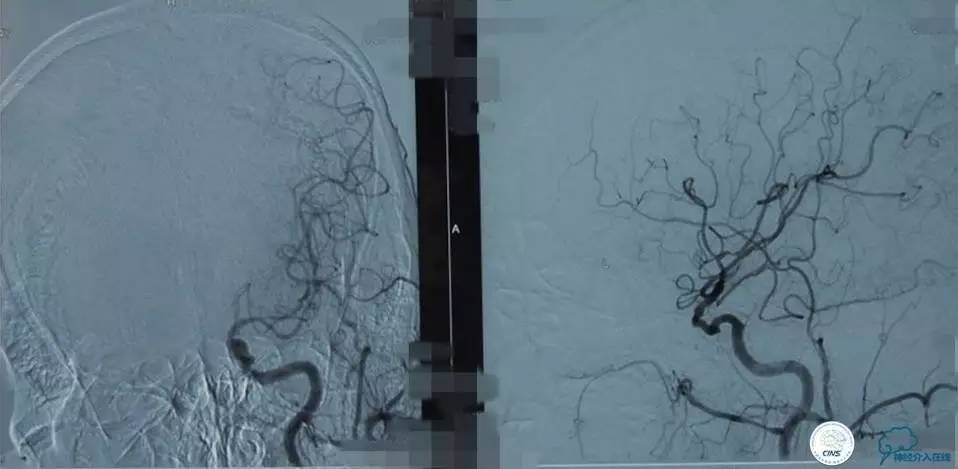

▼右M1闭塞-机械取栓

▼6F Neuron经8F导引导管

▼Solitaire FR到位

▼取出Solitiare后

▼术后第2天颈部+颅脑CTA